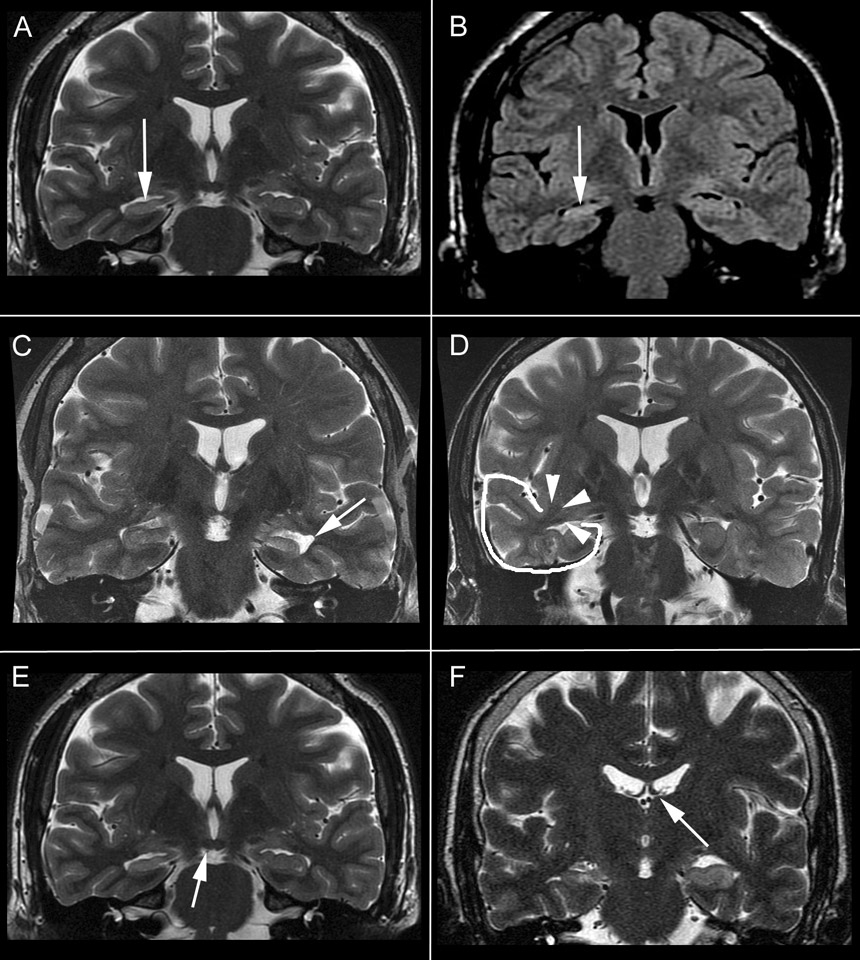

Figure 1

Primary- and secondary findings in mesial temporal sclerosis. A and B, Coronal T2 and Flair brain MR images showing atrophy and hyperintensity in the right hippocampus (white arrows). C, choroidal fissure dilatation. D, temporal lobe atrophy (white contour) and collateral white matter atrophy (white arrow heads). E, mamillary body asymmetry. F, fornix asymmetry.